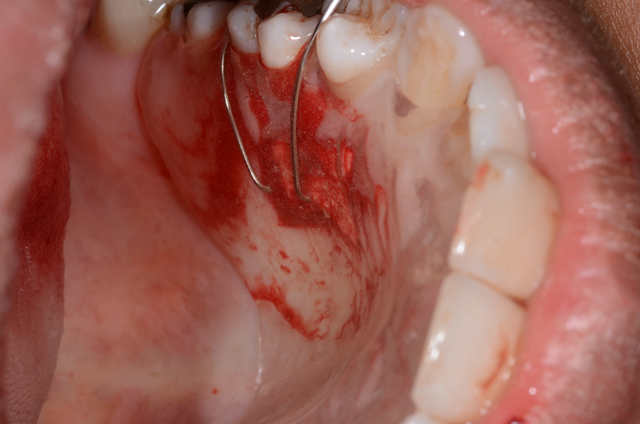

Voila, c`est ma deuxième GGL. Il y avait 0.5mm de gencive attachée sur la 41. On voit la cicatrisation à 48 heures.